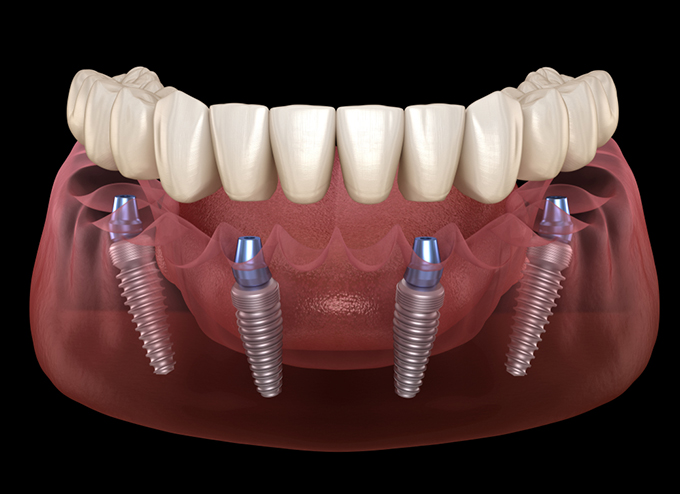

Trồng răng implant all on 4 hoặc all on 6 là phương pháp phục hình lại răng mất vợi sự kết hợp giữa cấy ghép implant và hàm giả tháo lắp. Khi thực hiện chân răng sẽ được trồng vào xương hàm tại một số vị trí nhất định, sau đó hàm giả sẽ được gắn cố định lên trên các trụ implant giúp phục hình lại những răng đã mất.

Trồng chân răng implant toàn hàm all on 4 đã được sử dụng phổ biến và khá lâu tại các nước như Mỹ, Anh, Đức… và hiện nay phương pháp này cũng đang dần phổ biến và được nhiều người tin dùng tại Việt Nam. All on 4 thay thế răng mất bằng cách cấy 4 trụ implant ở mỗi hàm để phục hồi khả năng ăn nhai, thẩm mỹ gần như răng thật.

Trồng răng implant toàn hàm all on 4 là một giải pháp phục hồi răng mất hiệu quả đối với trường hợp mất toàn bộ răng trên cung hàm. Tuy nhiên trồng răng toàn hàm có chi phí bao nhiêu và ưu điểm như thế nào thì là thắc mắc của rất nhiều cô/chú, anh/chị. Trong bài viết dưới đây chúng tôi sẽ giải đáp để quý cô/chú, anh/chị hiểu hơn về điều trị này.